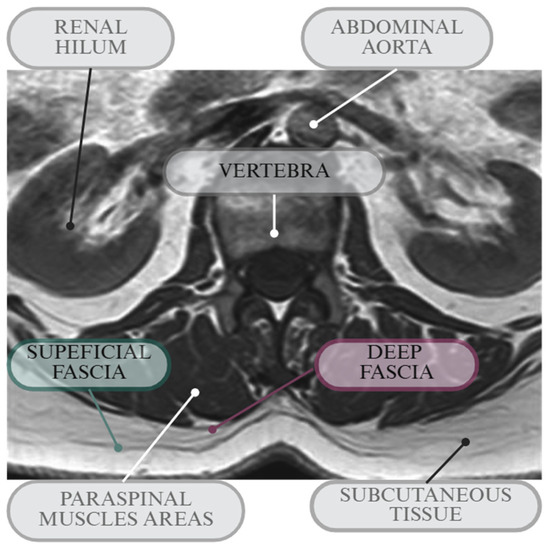

3.1. Deep Fascia Thickness

3.2. Superficial Fascia Thickness

3.3. Subcutaneous Tissue Thickness

4. Discussion

4.1. Answer to Research Question 1: Typical Thickness Values and Variability for SF, DF, and Subcutaneous Tissue in the Thoracolumbar Region in Asymptomatic Individuals

4.2. Answer to Research Question 2: Thickness Variability in Relation to Factors Such as Clinical Conditions (i.e., Non-LBP vs. LBP Individuals), Age, Sex, and Surrounding Structures